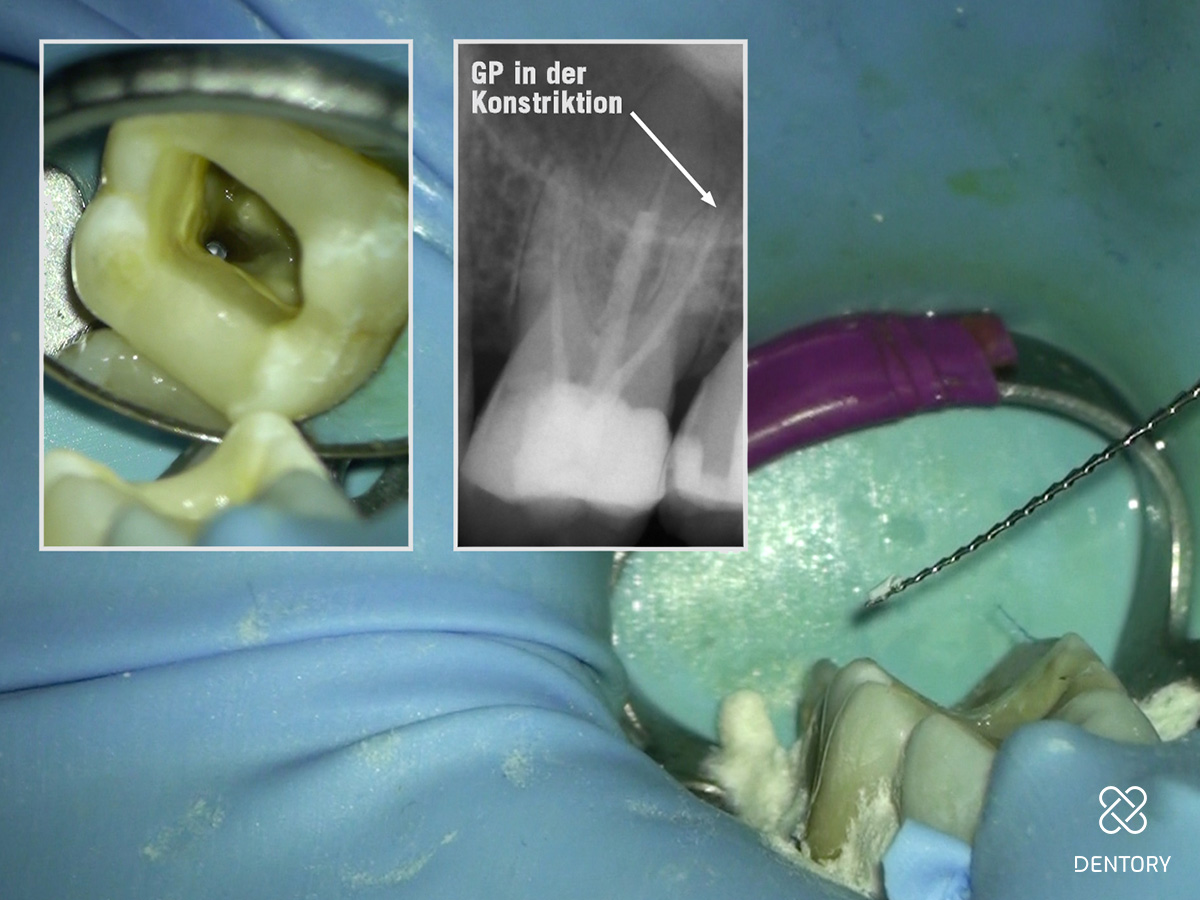

Abbildung 2

Röntgenologische Ausgangssituation.

Abbildung 8

Händische Guttapercha-Entfernung: Entfernung der Guttapercha, die über die Konstriktion hinaus geht mit einer Hedström-Feile ISO 25.